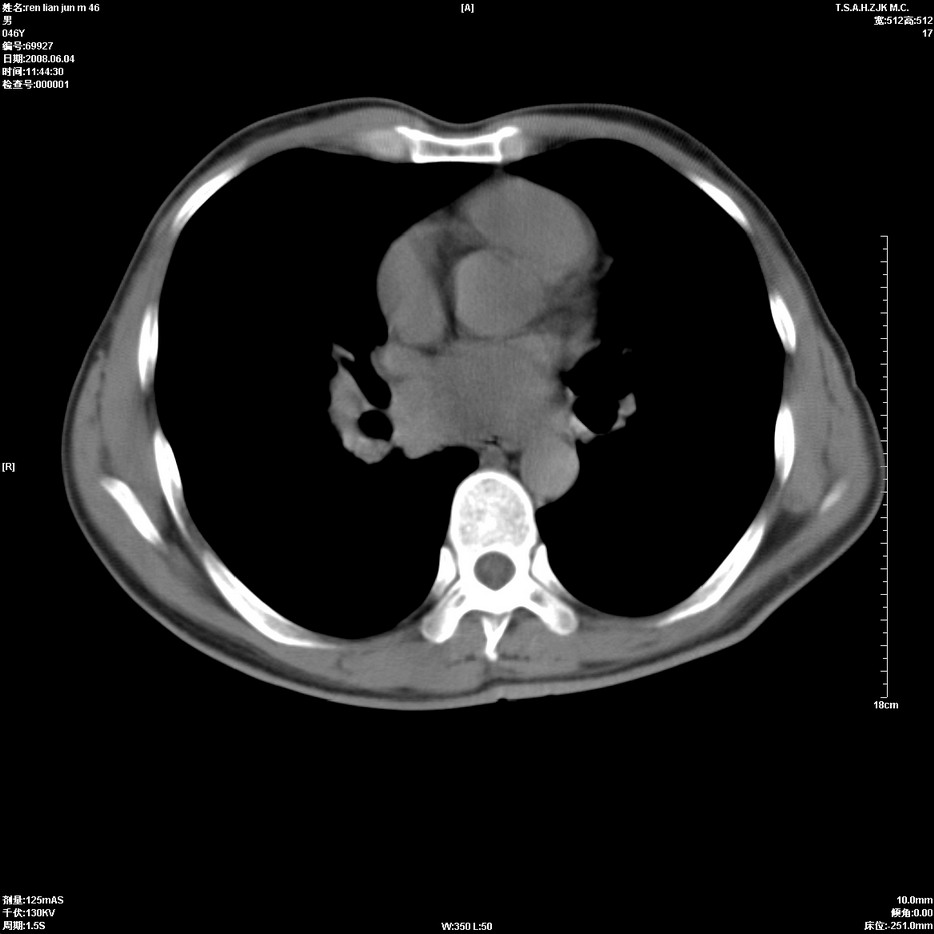

以下是引用qiu999在2008-6-5 17:14:00的发言:[br]考虑右肺中心型肺癌.颅内应做增强检查.

以下是引用形影不离在2008-6-5 19:18:00的发言:[br]右肺中心型肺癌并纵隔及左侧腋窝淋巴结转移,颅内应做增强检查。

以下是引用杀毒软件在2008-6-5 18:33:00的发言:[br]支持考虑右肺中心型肺癌,颅内病变是不是转移,不好说